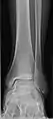

- Ankle - AP/Mortice and Lateral

Ankle - frontal

15 degrees internal rotation

Lateral (this one a bit suboptimal by not seeing straight through the ankle joint)

Lateral oblique (to visualize the posterior border of the tibia)